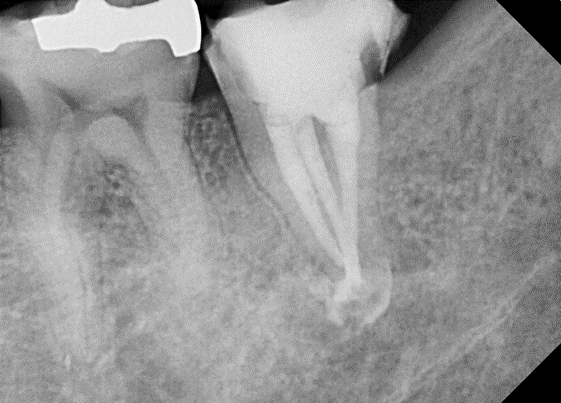

![[신경치료] 아래 어금니를 신경치료 할 때 치료할 때 알아야 할 것 (C형근관,고난이도치료) 관련 이미지 9](https://pub-9f2bb3498faf4d1d8714b41df24753e3.r2.dev/content/clinics/archive/nqmm0udu86/naver_blog/honeybeevuvu/assets/by_hash/fd9894626b80ca017415b65191ddb6fdf8dc092b65cd5990929c538cd1085212.png)

본원의 C형 근관 치료 예시 -30대 여성